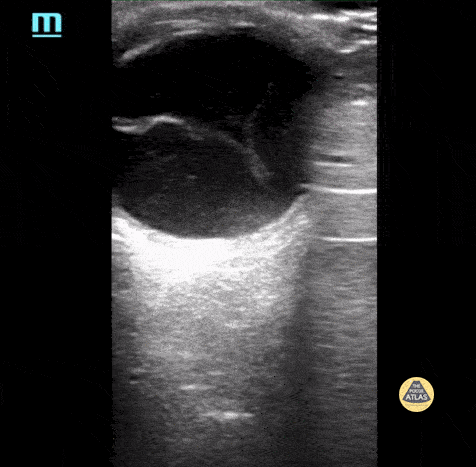

Retinal detachment. Please note how the retina is floating the posterior chamber and is anchored to the optic disc posteriorly. Contributor: Maher M. Abulfaraj, MD, @mahermabulfaraj